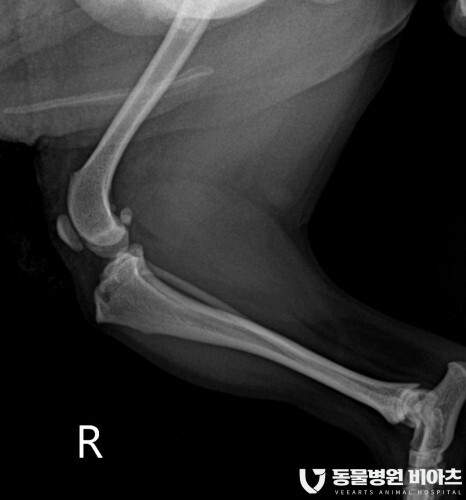

엑스레이 검사 결과

#전십자인대단열

#좌측 후지 슬개골 탈구 3기

#우측 후지 슬개골 탈구 2기

진단이 나왔습니다.